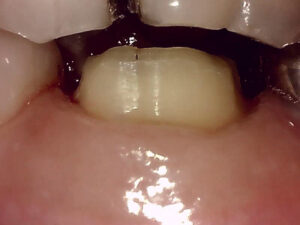

同年1/29 できてきたファイバーコアの土台をset

保険診療であれば仮歯調整して今回は終了し

次回形成と印象になりますが

患者さんに時短の説明をし納得いただけたので

続けて形成した後に印象を取り仮歯の調整まで

2時間超で自費診療:26000円+技巧代7600円

同年2/19 最短で根の処置から被せるまでこぎ着け

E-max set 自費:75000円

仮歯との違い と セラミックと金属の見た目

口腔内写真で明らかに違いが判るのは

保険で銀歯→ 自費で白い歯→